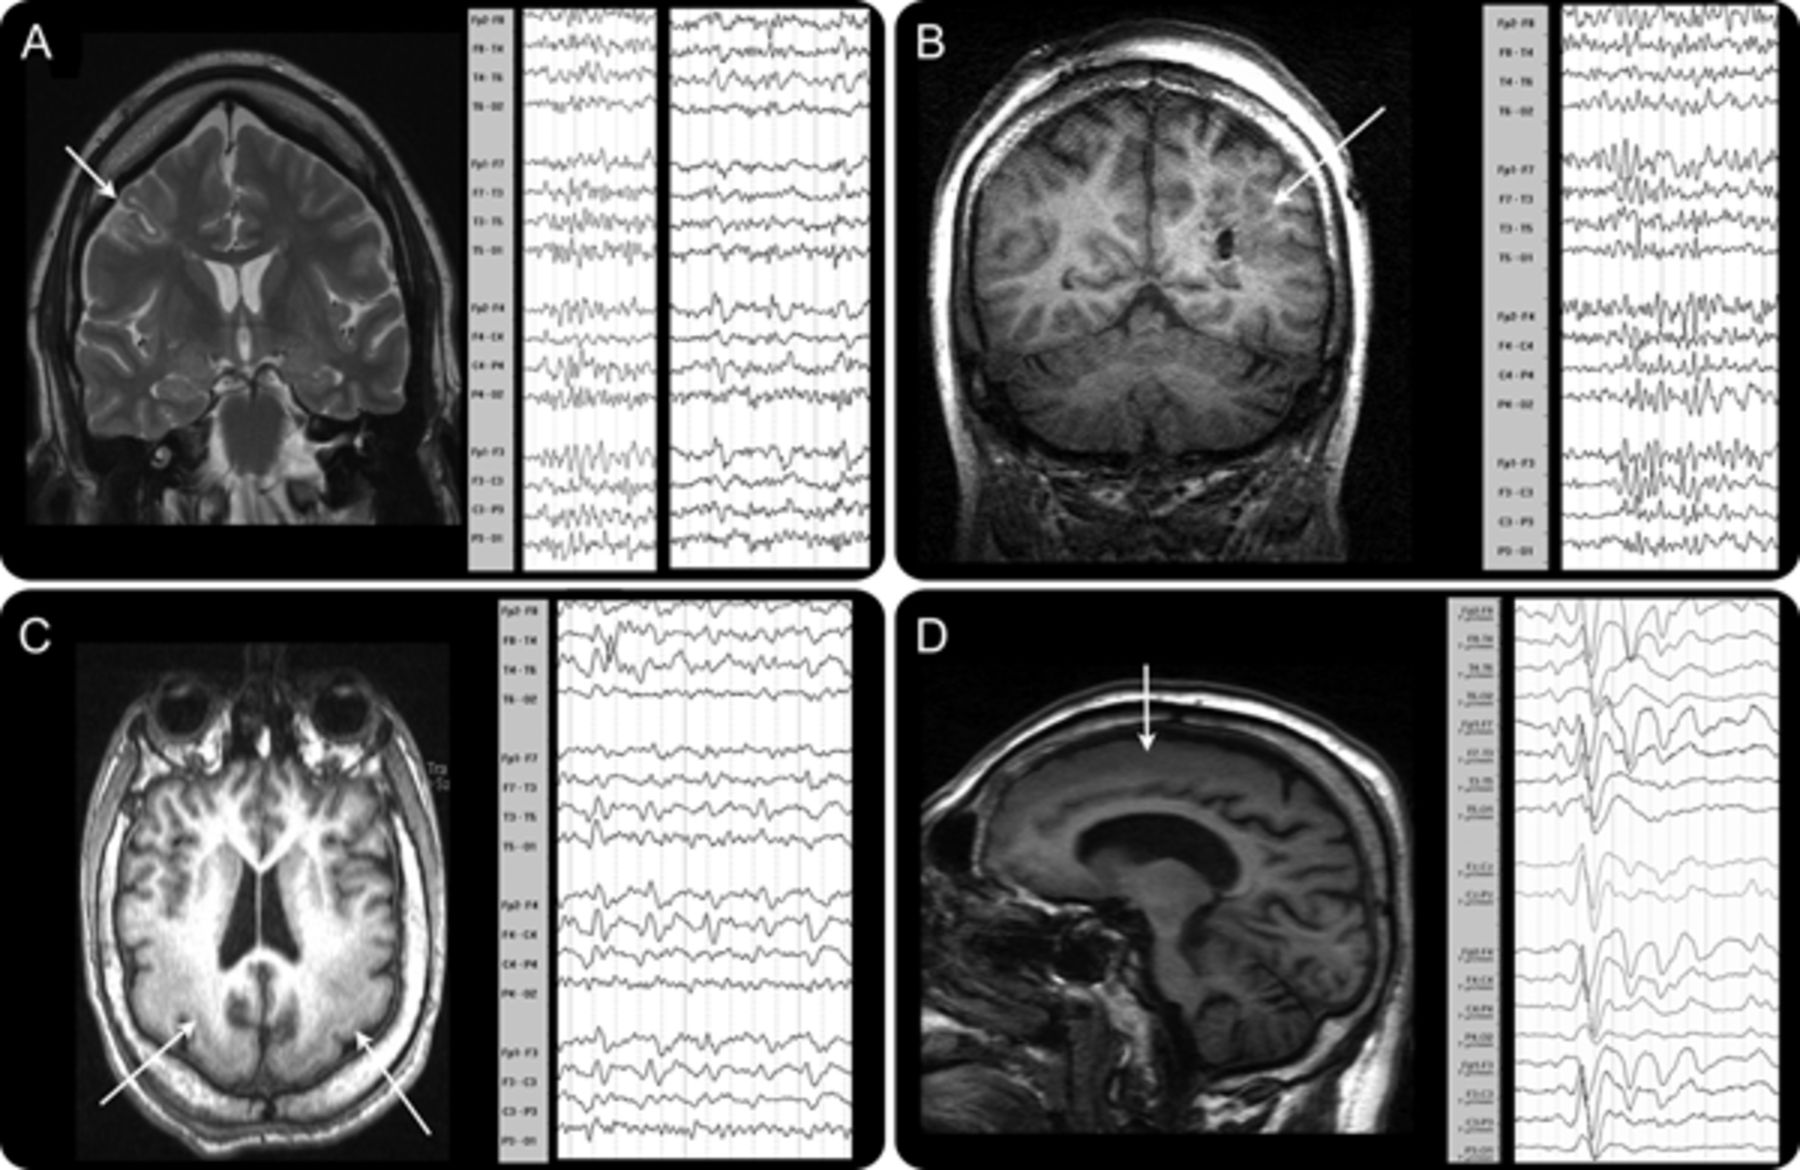

结构异常。

10例(77%),MRI异常(皮质畸形发展(MCD) 5)。这个组织的损伤变化很大程度上考虑到类似癫痫表型。焦发育和创伤性损伤是常见(图1中,得了)。1和3的病人,我们发现明确的结构性损伤,没有发现,一个重要的考虑因素在老年患者被宠坏的gradient-echo成像可能没有被反映在他们的早期,后来制度化和保守的管理。

焦点和边音的放电。

焦简易爆炸装置被记录在2例(4和11如图依照病人)。两个独立的焦点是记录在病人4(一左一右)。局部放电与皮质激活相关的整合与简易爆炸装置。

前两个病人、胼胝体(病人4和11,图4)。在这些患者中,PFA排放不定地显示正确,或者发出强调。这些边音的PFA排放相应产生的单侧性的招聘网络上面描述。

超出了一般的发现与PFA和f组报告上面,我们也指出,在一些患者中,即使脑电图似乎是广义,大胆的信号特点,甚至建议focality排放有单侧性的特性。在所有情况下,这些研究结果和病人的脑电图或结构的发现一致。这表明皮质病变可以激活连同这协会的扩散激活网络(DANA),可能拉拢它作为癫痫网络或至少参与这个系统在LGS癫痫活动。EEG-fMRI地图可以显示DANA和一个由癫痫引起的关注,可能会推动网络不稳定。在LGS、胼胝体切开之前,患者主要单方面DANA变化被认为与单边PFA排放。这表明网络在每个半球能够独立LGS招募和维持这种干扰网络活动(见图飞行)。